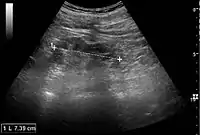

Kidney ultrasonography is useful for diagnostic and prognostic purposes in chronic kidney disease. Whether the underlying pathologic change is glomerular sclerosis, tubular atrophy, interstitial fibrosis or inflammation, the result is often increased echogenicity of the cortex. The echogenicity of the kidney should be related to the echogenicity of either the liver or the spleen (Figure 22 and Figure 23). Moreover, decreased kidney size and cortical thinning are also often seen and especially when disease progresses (Figure 24 and Figure 25). However, kidney size correlates to height, and short persons tend to have small kidneys; thus, kidney size as the only parameter is not reliable.[48]

Chronic renal disease caused by glomerulonephritis with increased echogenicity and reduced cortical thickness. Measurement of kidney length on the US image is illustrated by '+' and a dashed line.[48]